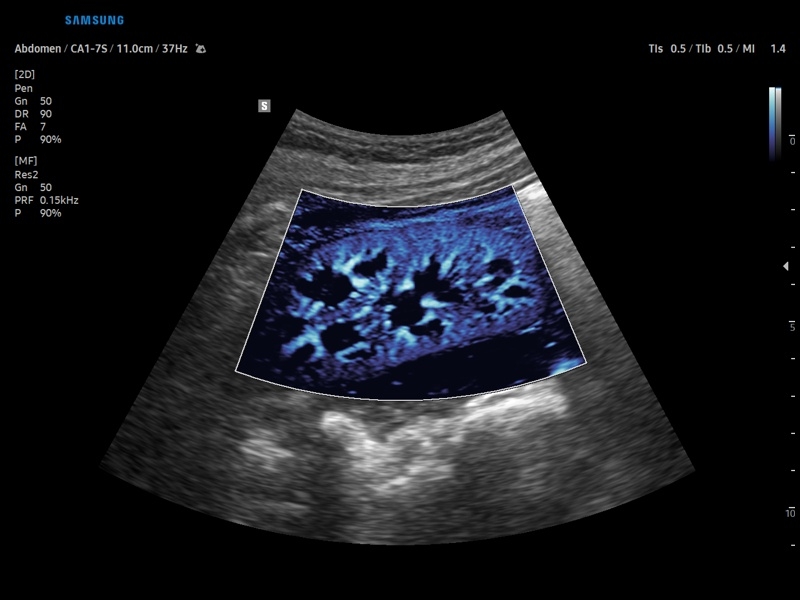

• Модуль MV-Flow – программа (режим), позволяющая визуализировать кровоток в микроциркуляторном русле с высоким разрешением без использования контраста.

• Модуль MV-Flow - программа (режим), позволяющая визуализировать кровоток в микроциркуляторном русле с высоким разрешением без использования контраста.